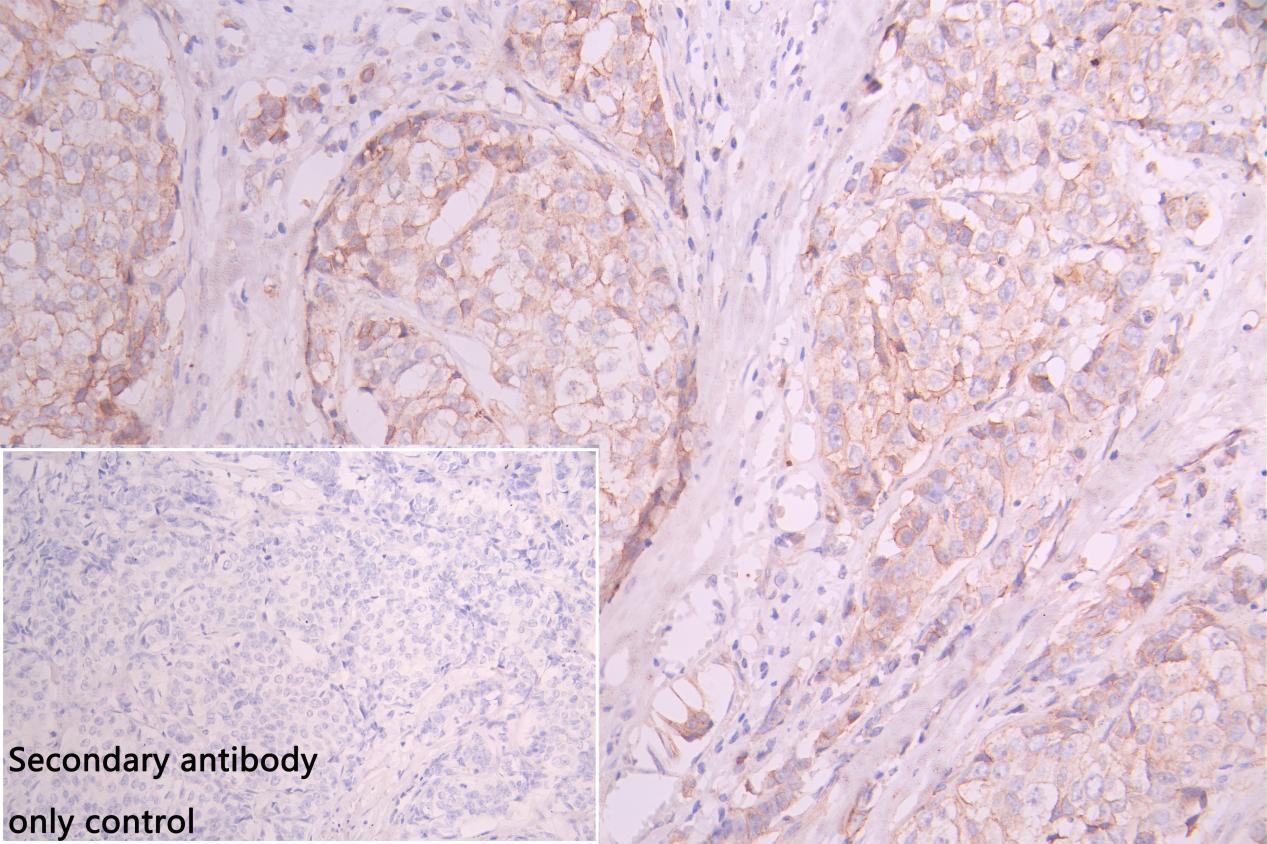

IHC image of CSB-PA015988LA01HU diluted at 1:100 and staining in paraffin-embedded human colorectal cancer performed on a Leica BondTM system. After dewaxing and hydration, antigen retrieval was mediated by high pressure in a citrate buffer (pH 6.0). Section was blocked with 10% normal goat serum 30min at RT. Then primary antibody (1% BSA) was incubated at 4°C overnight. The primary is detected by a Goat anti-rabbit polymer IgG labeled by HRP and visualized using 0.05% DAB. Secondary antibody only control: uses 1% BSA instead of primary antibody